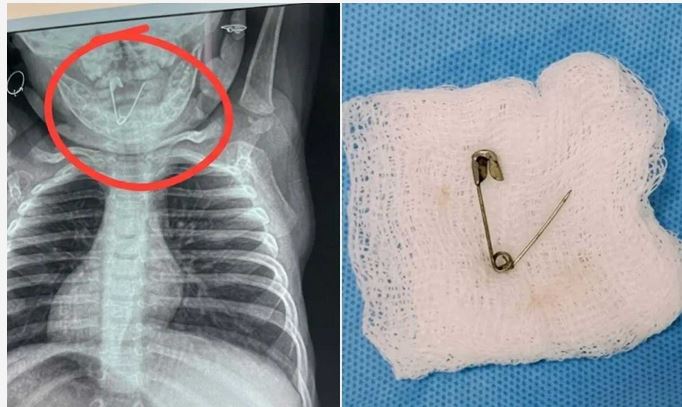

डॉक्टरों की सलाह पर बच्चे का एक्स-रे कराया गया। रिपोर्ट देखते ही मेडिकल टीम के होश उड़ गए, क्योंकि बच्चे के गले में एक खुली हुई सेफ्टी पिन फंसी हुई थी। यह स्थिति बेहद खतरनाक थी, क्योंकि पिन किसी भी समय अंदर खिसककर जानलेवा साबित हो सकती थी।

डॉक्टरों ने तुरंत रत्नागिरी के नवजात का ऑपरेशन करने का निर्णय लिया, लेकिन सर्जरी शुरू होने से पहले ही स्थिति और गंभीर हो गई। सेफ्टी पिन गले से फिसलकर भोजन नली (इसोफेगस) में पहुंच गई। इससे जोखिम कई गुना बढ़ गया और जरा सी चूक भी बच्चे के लिए घातक साबित हो सकती थी।

इस नाजुक परिस्थिति में ईएनटी विशेषज्ञों ने सूझबूझ दिखाते हुए एसोफैगोस्कोपी तकनीक का सहारा लिया। इस प्रक्रिया के जरिए बेहद सावधानीपूर्वक पिन को बाहर निकाला गया। ऑपरेशन के दौरान हर पल चुनौतीपूर्ण था, लेकिन डॉक्टरों ने धैर्य और सटीकता के साथ इसे सफल बनाया।